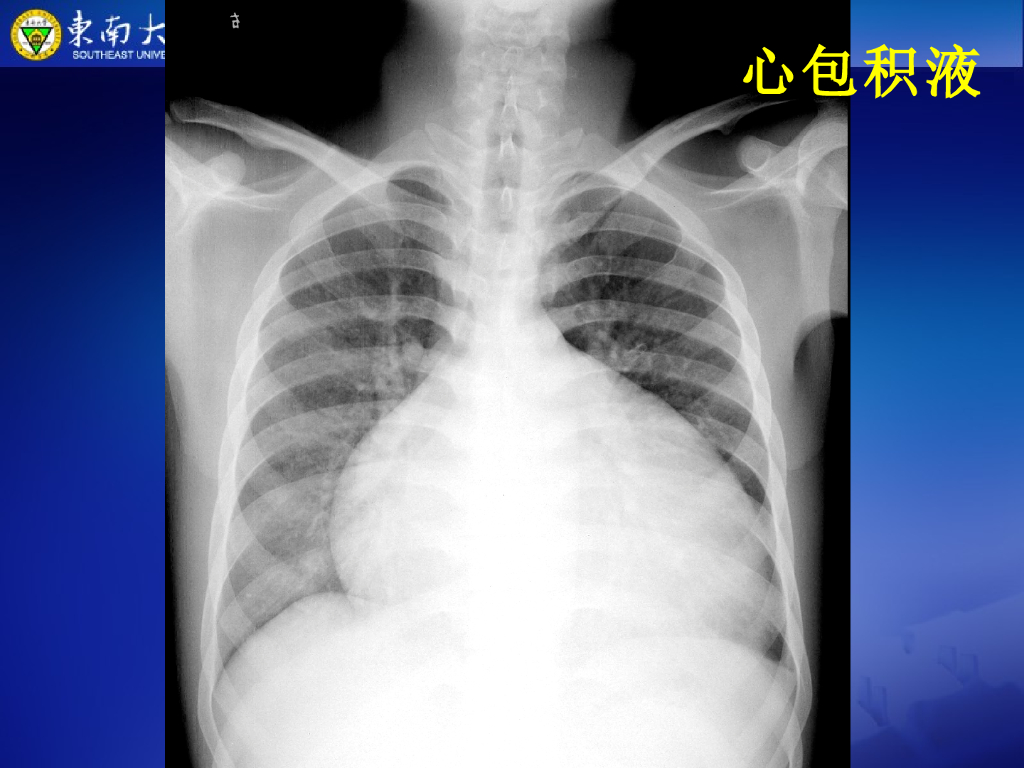

《放射诊断学》演示文稿-心肌、心包病变--实习.pdf